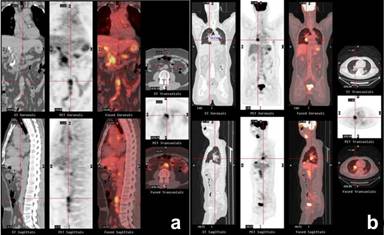

A 53-year-old white male, nonsmoker, was self-referred to our clinic for an enlarged prostate. Past medical history was significant for “idiopathic” pancreatitis (10 years ago), which resulted in diabetes mellitus type 2, benign prostate hypertrophy (for 4 years), asthma, and hypothyroidism. He complained of having a weak urine stream for 4 months. Prior to coming to our institution, the patient had a biopsy of the hard palate secondary to soft tissue inflammation; immunostaining was positive for IgG4 cells. Hence, systemic IgG4-related sclerosing disease was suspected. PET/CT, which was performed at our center, showed a diffuse tracer uptake by the prostate (Figure 5). In addition, it also revealed several hypermetabolic lesions in the salivary glands, thyroid (Figure 6), both bronchi, right hilar lymph nodes, right middle lung lobe (Figure 7), pancreas (Figure 8), and left kidney (Figure 9). PET/CT images were consistent with systemic IgG4-related sclerosing disease. Also, immunostaining of the prostate at our institution demonstrated a high number of IgG4-positive cells in high power field (Figure 10). IgG level was high (2,260 mg/dL); IgG4 level was not obtained. IgE was elevated (IgE: 1,125 KU/L). Prostate-specific antigen was normal (0.13 ng/mL; reference range: 0-4.00 ng/mL). Prednisone 40 mg daily was initiated and benign prostate hypertrophy symptoms resolved after one month of treatment. A two-month follow-up PET/CT showed resolution (Figure 11). Currently, the patient has been tapering off the prednisone and is asymptomatic.

Figure 11. Serial coronal and sagittal pre- (a.) and post-corticotherapeutic (b.) PET maximum intensity projection (MIP) images show complete resolution of the diffuse hypermetabolic lesions of systemic IgG4-related sclerosing disease. The focus at the left upper anterior chest wall represents an artifact (b.). Case#2. S: salivary glands; T: thyroid gland; H: bilateral hilar nodes; L: right middle pulmonary lobe; K: upper pole of the left kidney; P: pancreas; PR prostate |